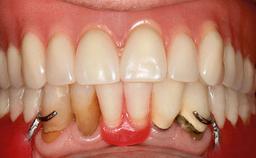

Improving an Existing Implant-supported Denture in an Alzheimer Patient with Bipolar Affective Disorder with Moderate Depression and Dementia

An 83-year-old man presented together with his caregiver at the dental department of the Medical University of Innsbruck, Austria with complaints of swelling in the right maxillary canine area and loss of retention of his 5-years-old mandibular denture. The patient had a significant medical history (20 years) of bipolar affective disorder with moderate depression (F 31.3) and dementia in Alzheimer’s disease (F 00.2). The patient had been in ambulant psychiatric therapy for his depressive illness for the past 20 years. He lived alone and had no children; his sister assisted with daily living. She reported that the patient exhibited compulsive hoarding behavior. In the previous two months, she had noted increasing disorientation and vertigo in the patient. She therefore accompanied him for a medical consultation at the Department of Psychiatry and Psychotherapy of the Medical University of Innsbruck. He was released home after a 6-week inpatient stay.

Prosthesis Type RDP